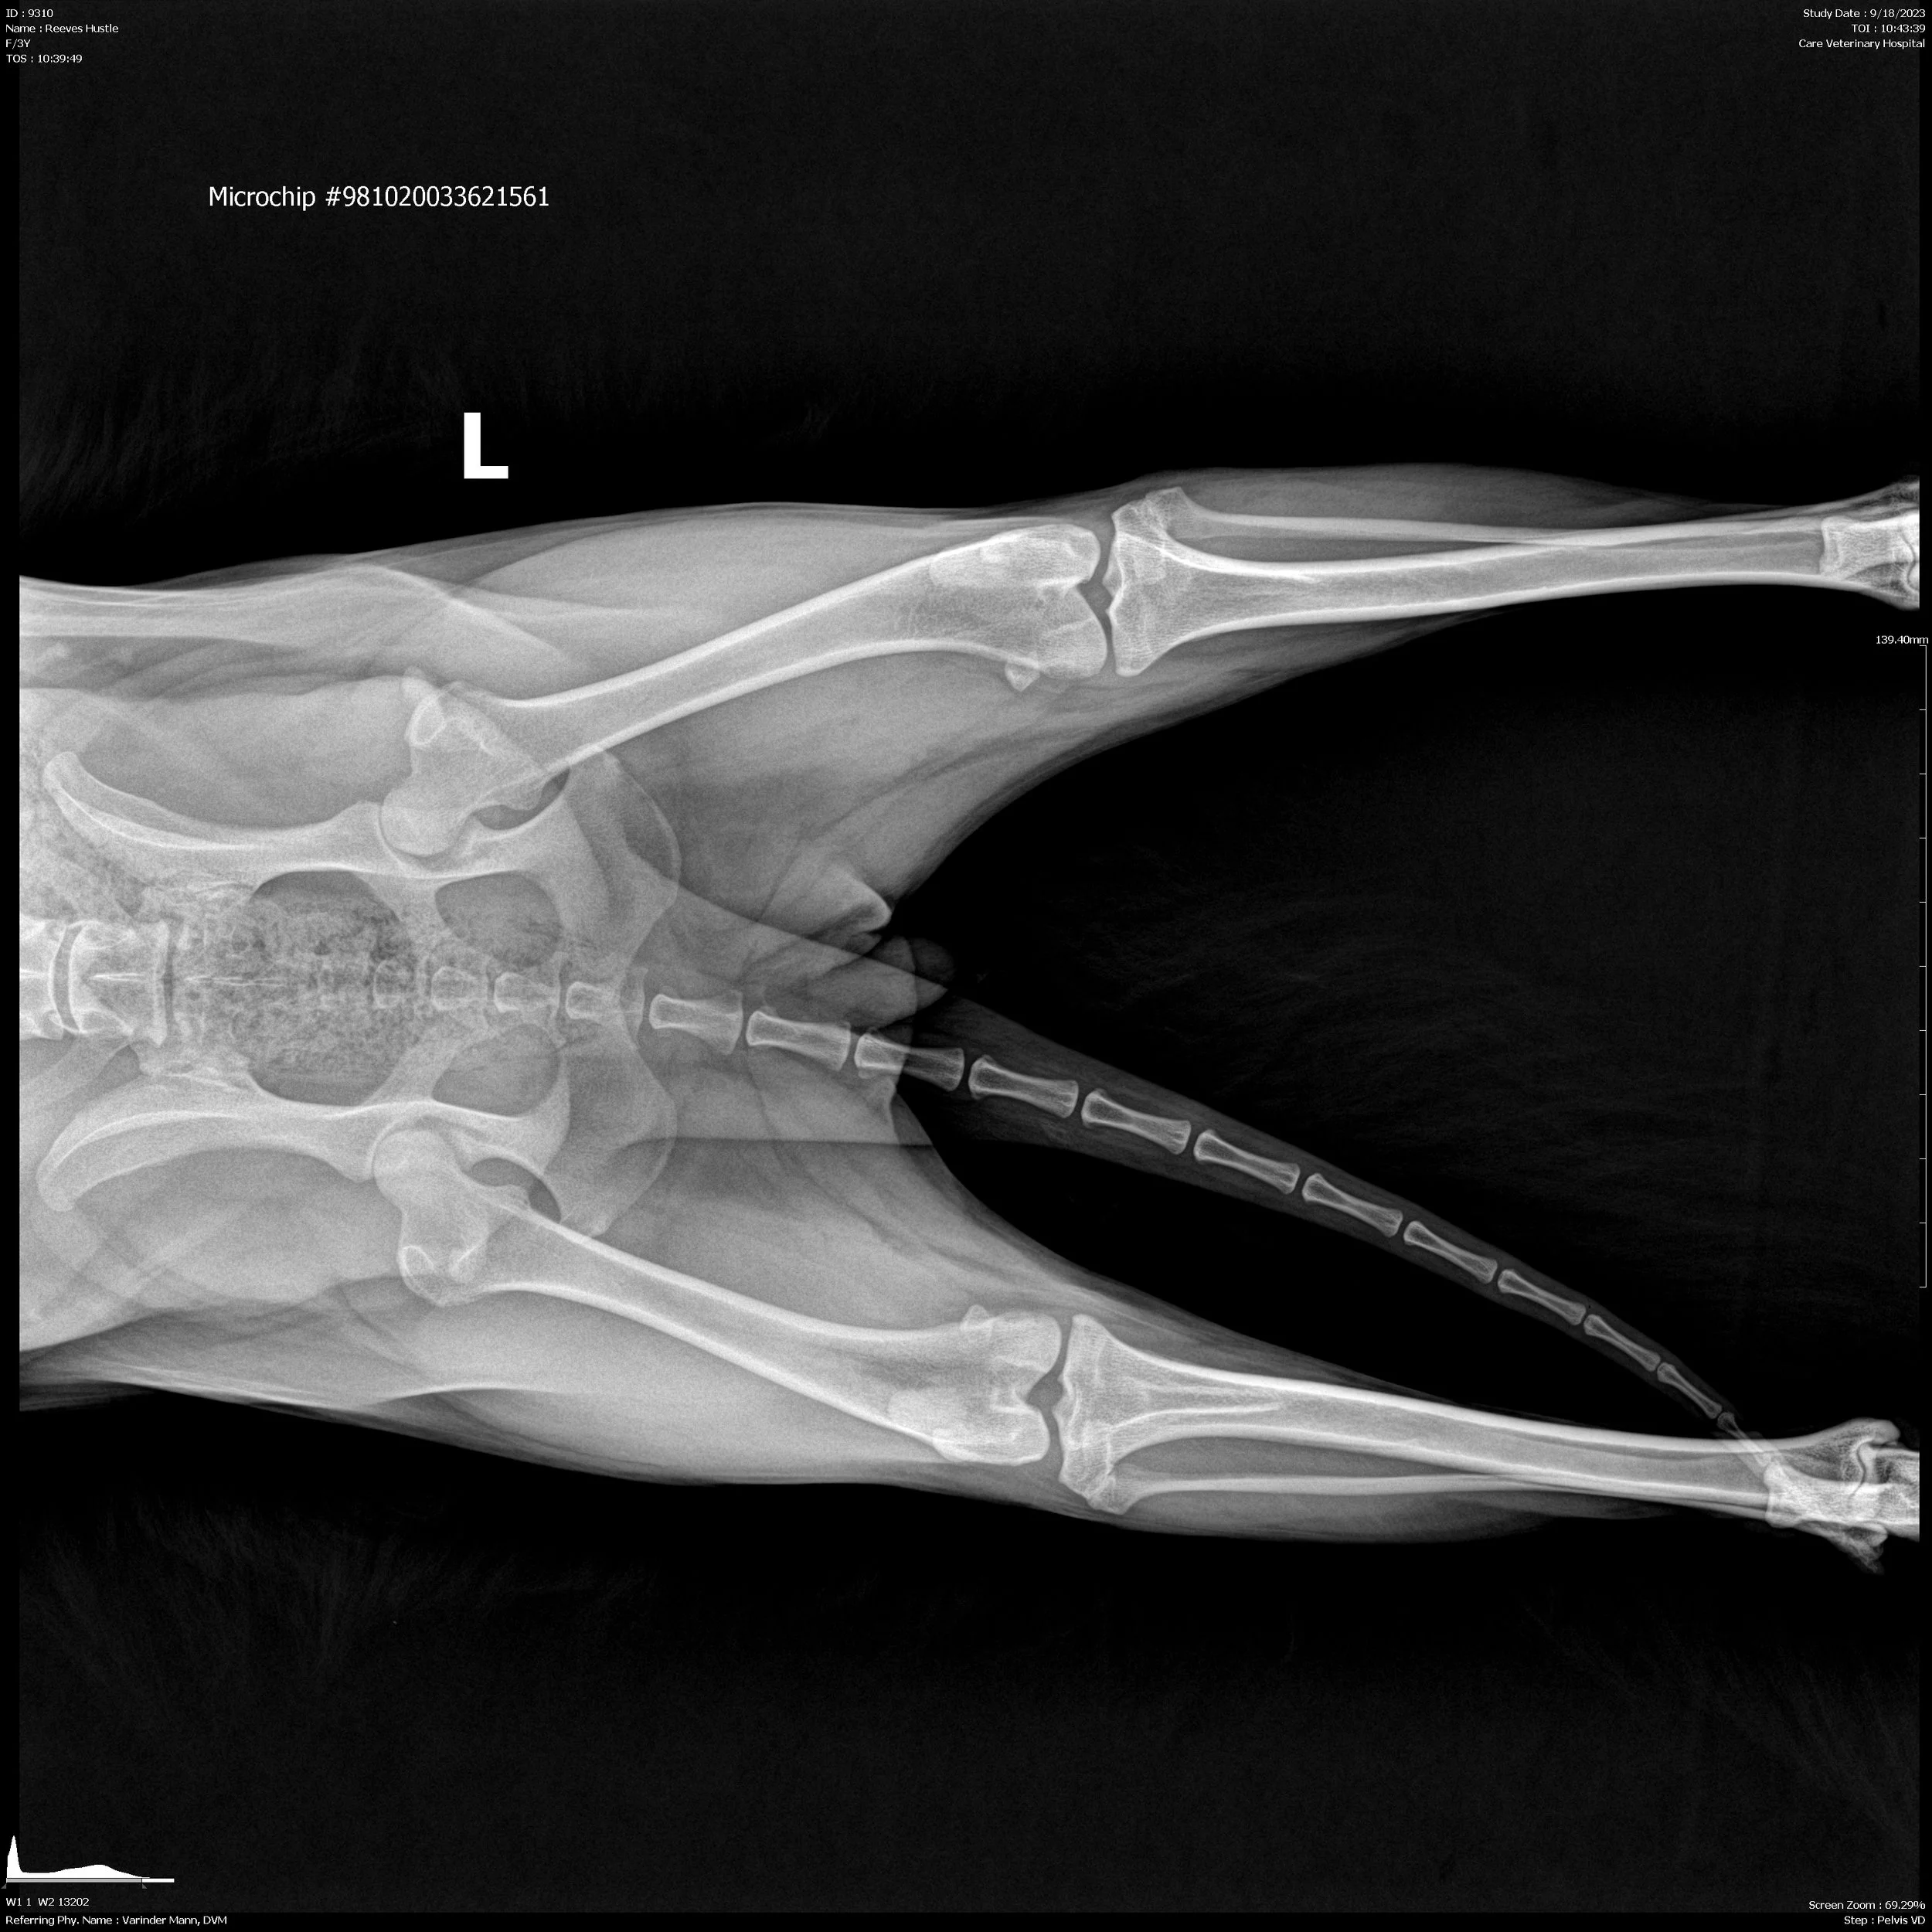

OFA Hips: Good

OFA Elbows: Normal